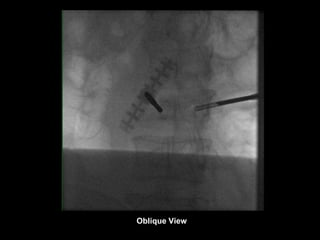

Oblique View